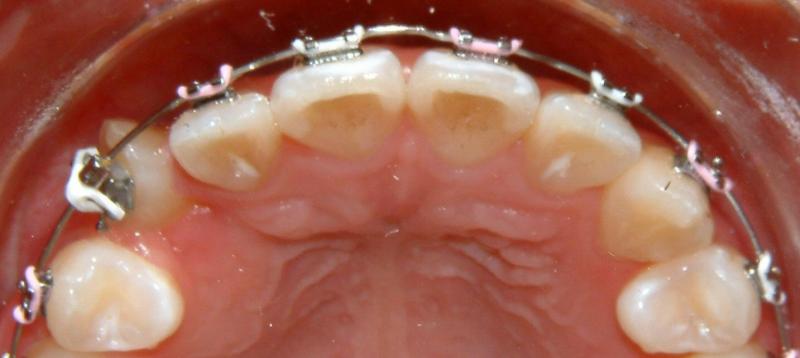

Without surgical exposure and forced eruption, there was practically very little progress with natural eruption of the upper right canine for nearly 3 years (not shown). With the surgical exposure (laser -> no bleeding) and forced eruption, the progress can be seen almost immediately - within a month (Fig. 9). After 2 months, the crown is more visible: part of the crown can be seen clearly (Fig. 10). After 8 months, the crown is moved into the position (Fig. 11). With additional 3 months, the crown is relatively well leveled and aligned (Fig. 12). It takes longer to treat the palatally impacted canine.

Fig. 10 Forced eruption, 2 months after surgical exposure (progress)

© Copyright 2007-2014, Vu Orthodontics. All rights reserved.